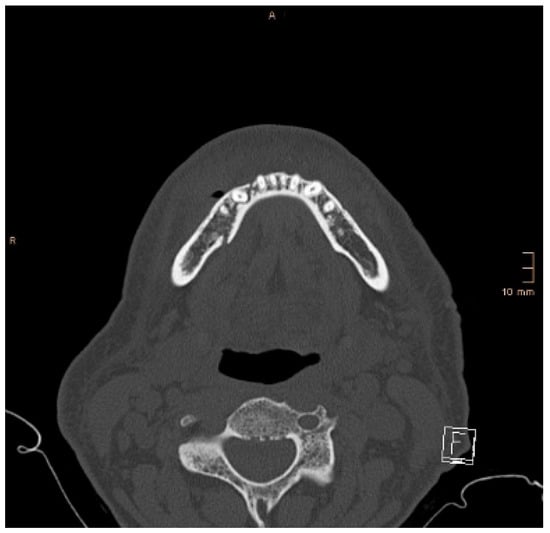

Figure 8 and Figure 9 below show another patient with a non-satisfactory reduction in the condylar neck fracture on the left-hand side due to a lingual gap present at a body fracture (Figure 8 and Figure 9).

Figure 9. Axial CT scan showing the same patient as in Figure 8. A lingual gap is present after ORIF of the mandibular body fracture, contributing to the inability to reduce the condylar fracture correctly.